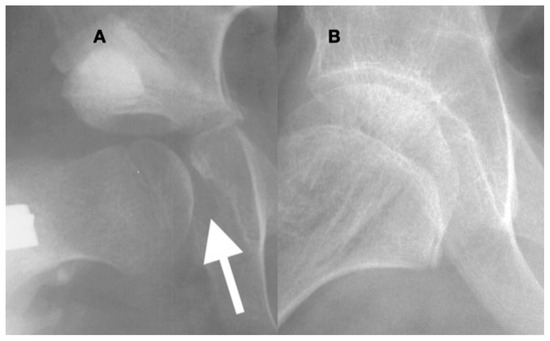

3.3.1. Impact of Abnormal Motor Function on Hip Development in Ambulatory Children

3.3.2. Pathology of Hip Development in Nonambulatory Children

3.3.3. Pathology of Hip Development in Children with Low Tone and Muscle Weakness

4.1.2. Pathologic Role of Coxa Valga and the Impact of its Correction in Weak and Hypotonic Hips

4.1.3. Pathologic Role of Coxa Valga and Treatment Options in Paralytic Hips